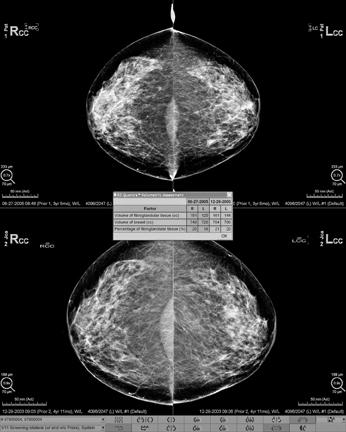

Mammogram reports sent to women often mention breast density Your health care provider can also tell you if your mammogram shows that you have dense breasts In some states, women whose mammograms show heterogeneously dense or extremely dense breasts must be told that they have dense breasts in the summary of the mammogram report that is sent to patients heterogeneously dense breast tissue (5175% glandular) extremely dense (>75% glandular) Breast density is subjective Different radiologists may give the same mammogram different ratings Use of computerized density measurement could alleviate interobserver variability, but there is not yet a standardized computer rating system For the purposes of the law, dense Heterogeneously dense breasts is a term used in mammography to describe breasts with a higher percentage of glandular and supportive tissue than fat It occurs in 40% of women and while normal, can make it more difficult to detect breast cancer on mammography Dr Margaret Polaneczky explains that, under this classification, the breast composition measures

Mammogram Question 40 years old and had mammogram This is what the report says Breast parenchyma is heterogeneously dense Focal asymmetry seen in upper central right breast which cannot be confirmed as stable Additionally, an asymmetry in the superior right breast, posterior depth which appears more prominent when compared to prior studies Dense breast tissue is a normal finding, and about half of all women have dense breast tissue If you have dense breast tissue, this means you have a higher proportion of glandular breast tissue to fatty tissue Having dense breast tissue can make it more difficult to see breast cancer on a mammogram Dense tissue appears white on a mammogram while fatty tissue appears black Breast One of the main problems with dense breast tissue is that it shows up as white on mammogram images Fatty breast tissue looks black in images Unfortunately, signs of breast cancer like tumors or calcifications also appear white in mammograms, making it difficult for doctors to detect abnormalities Additional breast screening techniques may be required to get a true picture of your breast

The normal breast31 The breast parenchyma, mammographic technique, and visibility of the mammary structuresSurrounding the glandular elements, lobules and mammary ducts, the connective tissue is made of two different elements a tissue poor in collagen fibres (tissue of the "mantle") which is subjected to important physiologic changes and a denseThe breast tissue is heterogeneously dense, which could obscure detection of small masses (approximately 51% 75% glandular) 4 Dense breasts occur when a woman has a high ratio of ligaments and glands compared to fat in her breasts If a woman has a high ratio of fat compared to everything else, the breasts are considered to be "fatty" "While younger women tend to have denser breasts, breast density is largely determined by your genetics," says Dr Campbell

D Extremely dense indicates that nearly all of the breast tissue is dense About 1 in 10 women has this result In general, women with breasts that are classified as heterogeneously dense or extremely dense are considered to have dense breasts About half of women undergoing mammograms have dense breasts The breasts are heterogeneously dense, which may obscure small masses (breast composition category c) (Patients in categories c and d may qualify for supplemental screening exams) The tissue undergoes marked background enhancement, increased from priorThe degree of normal fibroglandular tissue that enhances on breast MRI, known as background parenchymal enhancement (BPE), was initially described as an incidental finding that could affect interpretation performance While BPE is now established to be a physiologic phenomenon that is affected by both endogenous and exogenous hormone levels, evidence supporting the notion that BPE frequently masks breast

Lumps, both benign and cancerous, also appear white So, mammograms can be less accurate in women with dense breasts If a woman's mammogram shows she has heterogeneously dense or extremely dense breast tissue, sheIII The breast is heterogeneously dense This may lower the sensitivity of mammography IV The breast tissue is extremely dense, which could obscure a lesion in mammography Examples of these breast types are shown in Figure 1 Other pattern classifications include the sixcategory classification (SCC)There are four descriptors for breast density on mammography in the 5 th edition of BIRADS 1,2 a the breasts are almost entirely fatty b there are scattered areas of fibroglandular density c the breasts are heterogeneously dense, which may obscure small masses d the breasts are extremely dense, which lowers the sensitivity of mammography

a The breast are almost entirely fatty Mammography is highly sensitive in this setting b There are scattered areas of fibroglandular density The term density describes the degree of xray attenuation of breast tissue but not discrete mammographic findings c The breasts are heterogeneously dense, which may obscure small massesA few areas of dense tissue are scattered through the breasts (about 40% of women) The breasts are evenly dense throughout (about 40% of women) The breasts are extremely dense (about 10% of women) Women in the first two categories are said to have lowdensity, nondense, or fatty breasts Women in the second two categories are said to have highdensity or dense breasts About half of women who are 40 years old or older have dense Qualitative measures include the Wolfe grade (N 1, normal fatty breast;